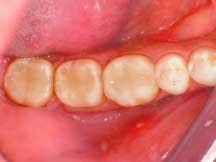

After applying the dentin material, the clinician placed a .5 mm layer of medium value enamel material, followed by the final layer of clear transenamel material, using the same buildup and curing technique as specified for the dentin layers. A final cure of each restoration was performed from the occlusal aspect for 30 to 40 seconds per tooth (Figure 4).

The interproximal areas were verified with floss and, in areas where any flash existed, a 12-B blade was used at the gingival margin in a gentle, carving motion to remove it (Figure 5). To reproduce the natural shape and anatomy of the teeth, a series of fine and super-fine diamond finishing burs (Axis Dental Corporation) were used. The occlusion was then checked and, where necessary, a pointed bur was used to reform the anatomy following any occlusal adjustments.

The rubber dam was removed, occlusion was checked and adjusted, and final polishing was completed using a green Jiffy polishing cup (Ultradent Products, Inc.) and Jiffy bristle brush. To best polish the gingival areas, a finishing strip (Epitex Strip) was used. Figure 6 shows the completed direct composite posterior restorations.

4

6